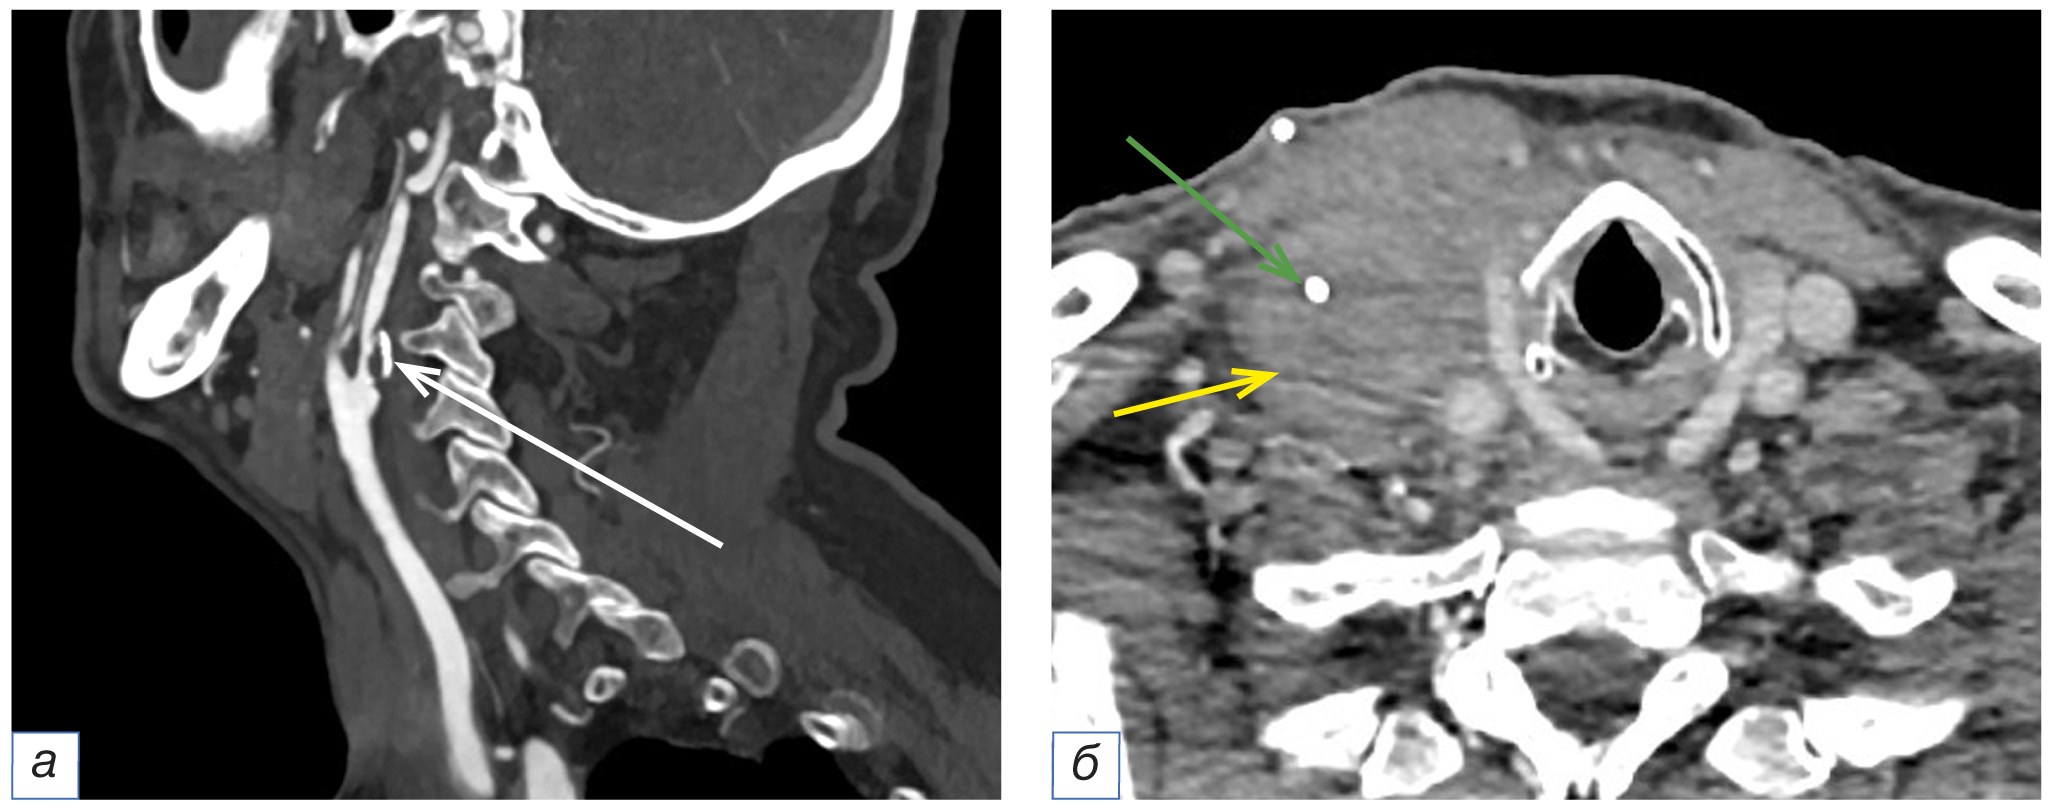

В 4 (6,5%) случаях в мягких тканях шеи не были описаны изменённые лимфатические узлы подбородочной области (группа Ia) и нижние ярёмные (группа IV). Все они были округлой формы размером от 10 до 14 мм, неоднородной структуры, слабоинтенсивно негомогенно накапливали контрастный препарат (рис. 5).

Рис. 5. Фрагменты компьютерных томограмм области головы и шеи в сагиттальной плоскости (а, б). У пациента в возрасте 63 лет с диагнозом рака красной каймы нижней губы рT3N0M0 определяется округлой формы подбородочный лимфоузел (группа Ia) с чёткими ровными контурами, неоднородно накапливающий контрастный препарат, размером до 11×9 мм (а, жёлтая стрелка). На контрольном исследовании через 3 месяца отмечается увеличение вышеописанного лимфоузла до 33×24 мм (б, жёлтая стрелка).

Fig. 5. Computed tomograms of the head and neck, sagittal planes (а, б). A 63-year-old patient with cancer of the red border of the lower lip pT3N0M0 has a round-shaped submental lymph node (group Ia) with clear, even contours, heterogeneously accumulating the contrast agent, measuring up to 11×9 mm (а, yellow arrow). A control study after 3 months showed the enlargement of the above-described lymph node to 33×24 mm (б, yellow arrow).